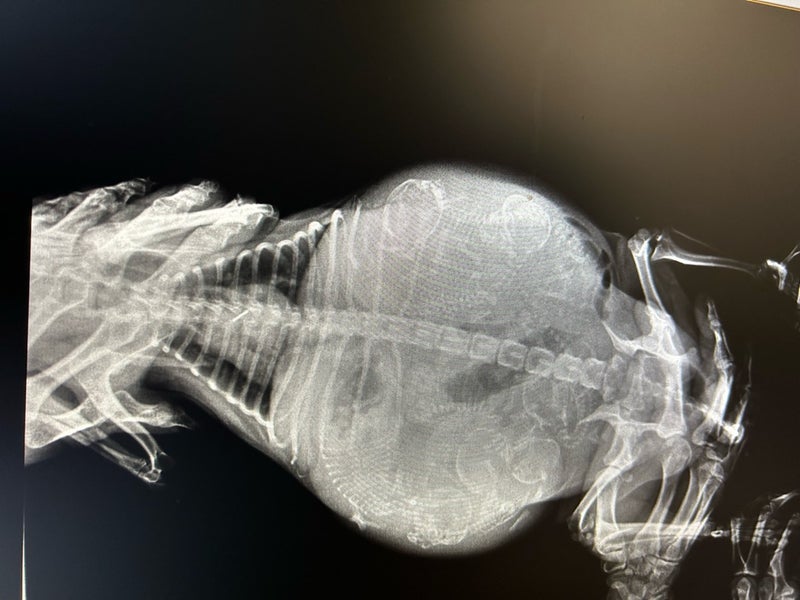

大きなお腹をしていましたので、何匹ベビーがいるのかと思っていましたが、レントゲンの結果、6ベビーが写っていました

出産は明日明後日あたりとのこと

今週末にはベビーに会えることでしょう